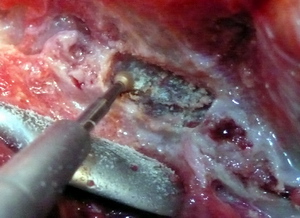

Con una gubia articulada cortando la apofisis.v